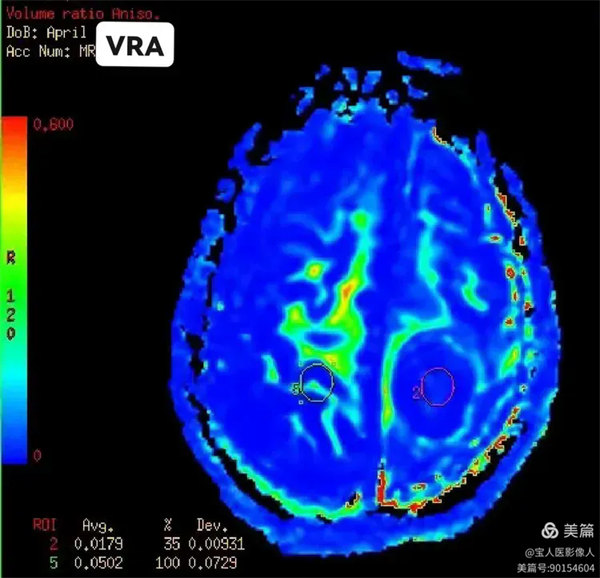

圖6:容積比(VRA):

病灶與相應正常對照側腦組織容積比數值對照。